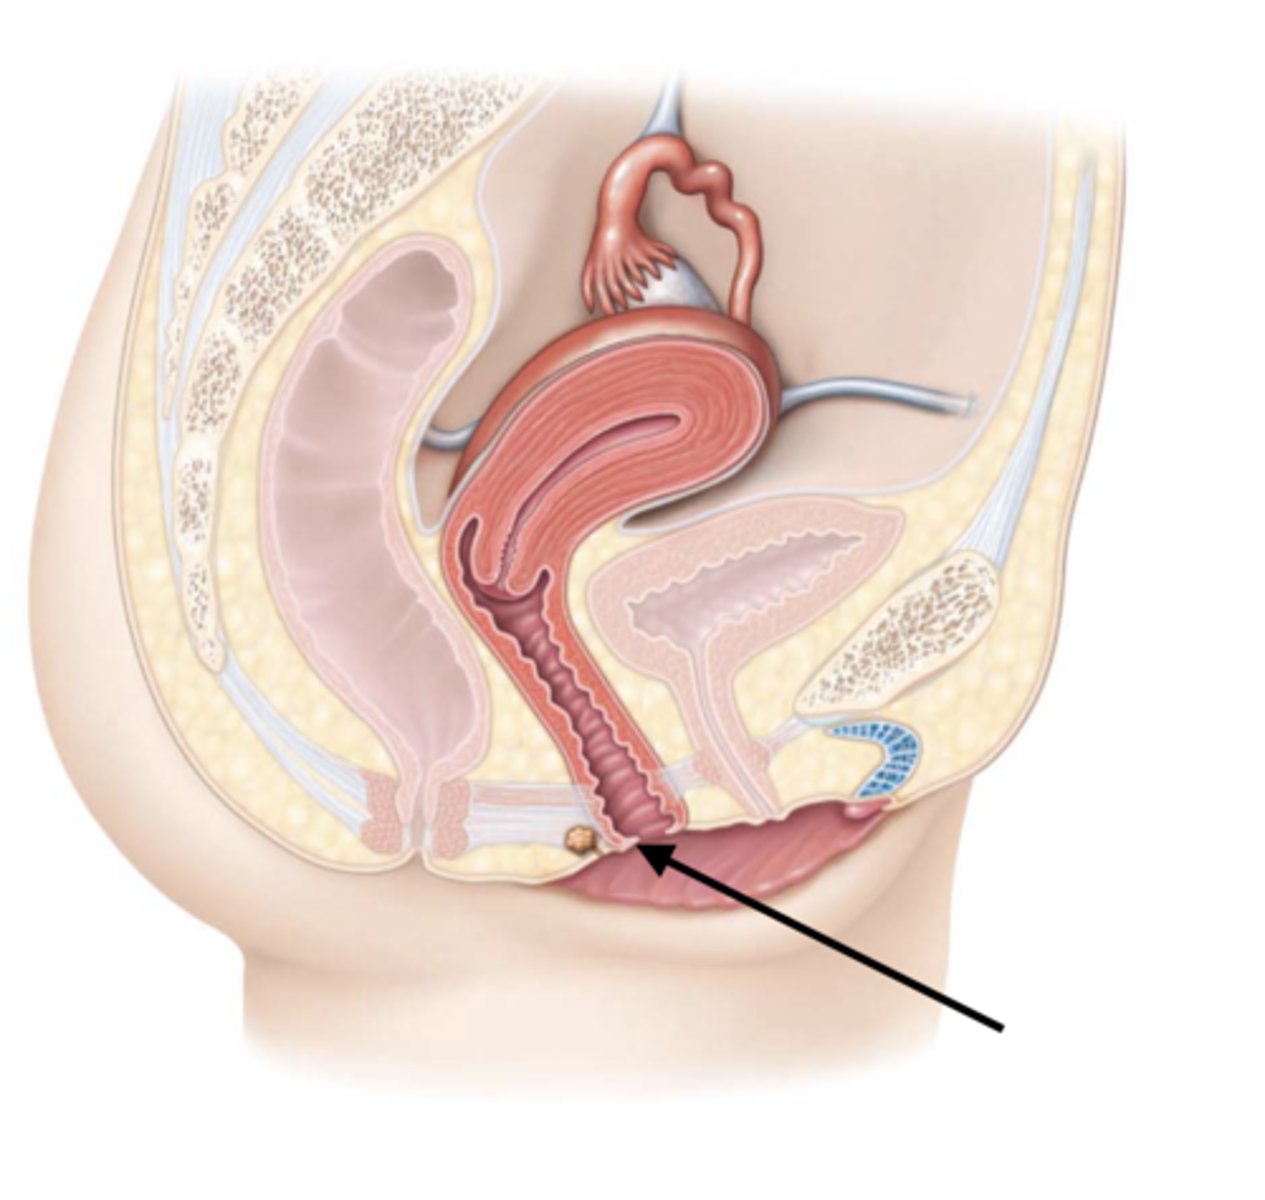

Vagina

Vaginal orifice

Hymen

Vaginal fornix

Fallopian tube

Fimbriae

Infundibulum

Ampulla

Isthmus

Uterus

Cervix

Internal os

Cervical canal

External os

Labia majora

Labia minora

Prepuce

Vestibule

Clitoris

External urethral orifice